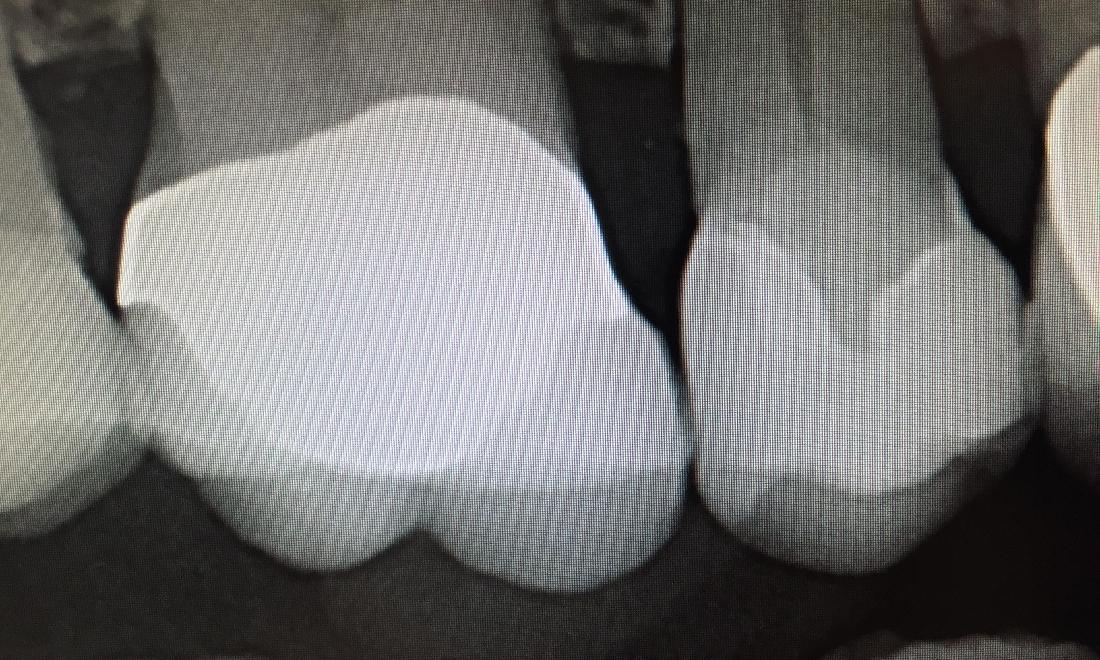

Poorly Contoured Restoration

Patient had a large amalgam filling with margin overhang the edge of the tooth, which can cause plaque and bacterial accumulation. This can potentially cause periodontal disease and tooth decay. The tooth was treated with all-ceramic crown to correct the overhang and prevent possible complications. Patient can now floss and maintain proper hygiene.